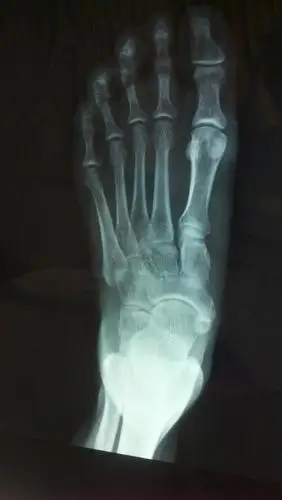

73岁男性,右足第一跖趾关节疼痛10年 - 骨科 -丁香园论坛

脚骨骼结构图

足骨骨折多久能好